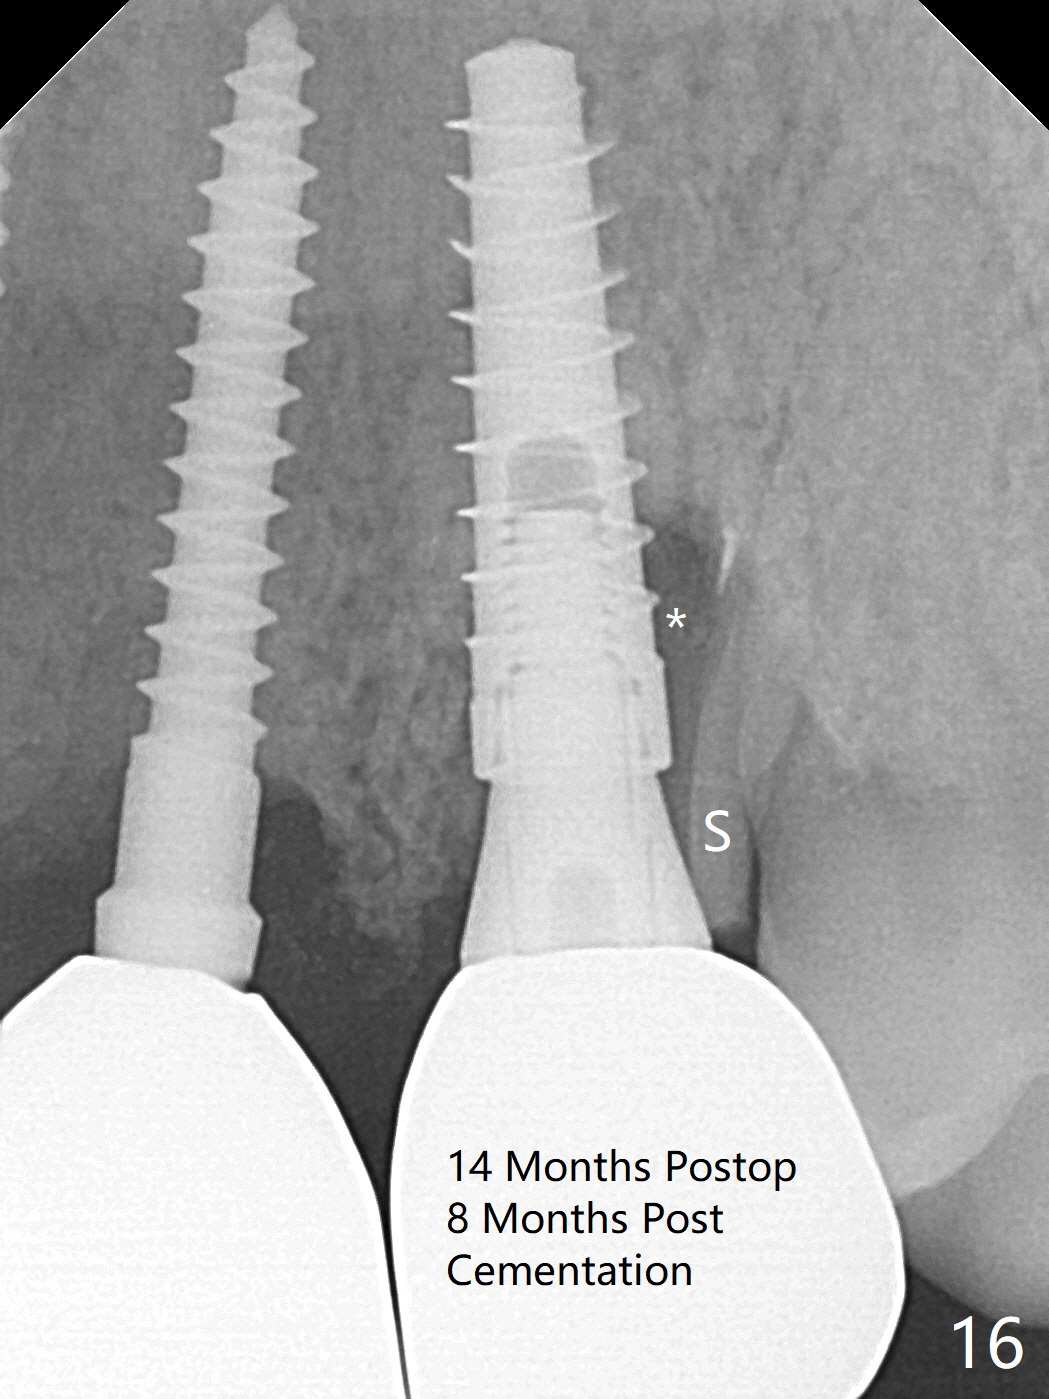

The buccal plate at #10 undergoes atrophy 9 months post immediate implant (Fig.1 *). To prevent the same post-extraction complication at #11, a technique called socket shield is going to be adopted. The buccal portion of the root (Fig.2-6 R, half-moon shaped) remains in place while a 3.5x13 mm implant is placed in the palatal portion of the socket (>50 Ncm). In fact the root is trimmed slightly subcrestal (Fig.6 C). It is assumed that there will be no or minimal bone resorption as long as the periosteum between the buccal plate and the remaining buccal root is not disturbed after tooth removal. After placement of a 4.5x15 degrees A (2mm) angled abutment and Vanilla graft (Fig.7 *), an immediate provisional is fabricated (using a central incisor crown form for #10 because of extra wide space of #11, Fig.8). There is no buccal plate atrophy at the canine 11 days postop (Fig.9). There is smooth transition from the grafted bone to the native bone 4.5 months postop (Fig.10). The buccal plate remains non-atrophic at the canine 4.5 months postop (Fig.11,12). CT taken 1 month post cementation shows that the implants at #10 and 11 are placed somewhat lingually (Fig.13,14 L (*: socket shield)). Gingival swelling is noted (Fig.15 *) with +Bleeding On Probing (^) 8 months post cementation (at the time of #21/24 impression). It appears that the socket shield (Fig.16 S) causes infection and loss of bone graft (*). The shield will be removed with an oblique accessory incision to save the papilla between #10 and 11 (Fig.17 black line). Prepare PRF for sticky bone (x1).